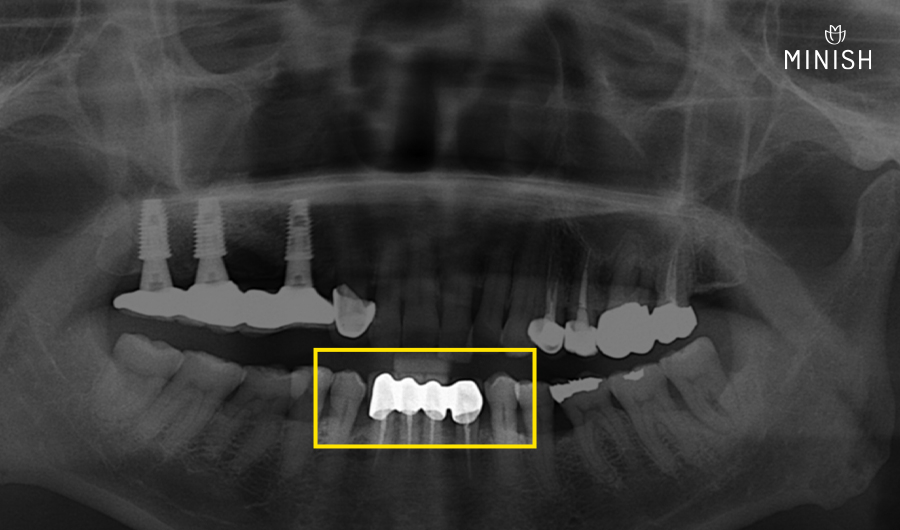

과거 크라운 브릿지 치료 속 상태

보철치료를 위해 무리하게 건강한 이의 표면을 삭제하는 바람에 신경치료까지 해야 했죠.

예전 치과에서 과도한 치아 삭제가 진행된 이유?

크라운은 어느 정도 두께가 보장되어야 단단한 강도를 유지할 수 있습니다.

두꺼운 크라운을 그대로 씌우면 뚱뚱한 모양이 되기 때문에 표면을 삭제해 크라운 공간을 마련합니다.